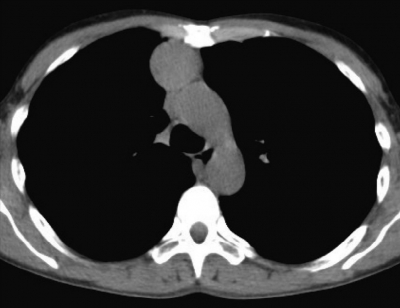

28歳の女性。健診で胸部の異常陰影を指摘されたため来院した。胸部エックス線写真と胸部CTとを示す。

診断のために必要性が低い検査項目はどれか。

a. hCG

b. β-Dグルカン

c. 可溶性 IL-2受容体

d. α-フェトプロテイン(AFP)

e. 抗アセチルコリン受容体抗体